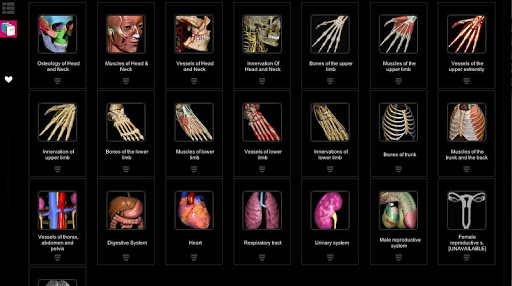

A true and totally 3D app for studying human anatomy, built on an advanced interactive 3D touch interface.

Features:

★ Both male and female reproductive systems are available

Contents:

★ Bones

★ Ligaments

★ Joints

★ Muscles

★ Circulation (arteries, vein and heart)

★ Central nervous system

★ Peripheral nervous system

★ Sense organs

★ Respiratory

★ Digestive

★ Urinary

★ Reproductive ( both male and female)